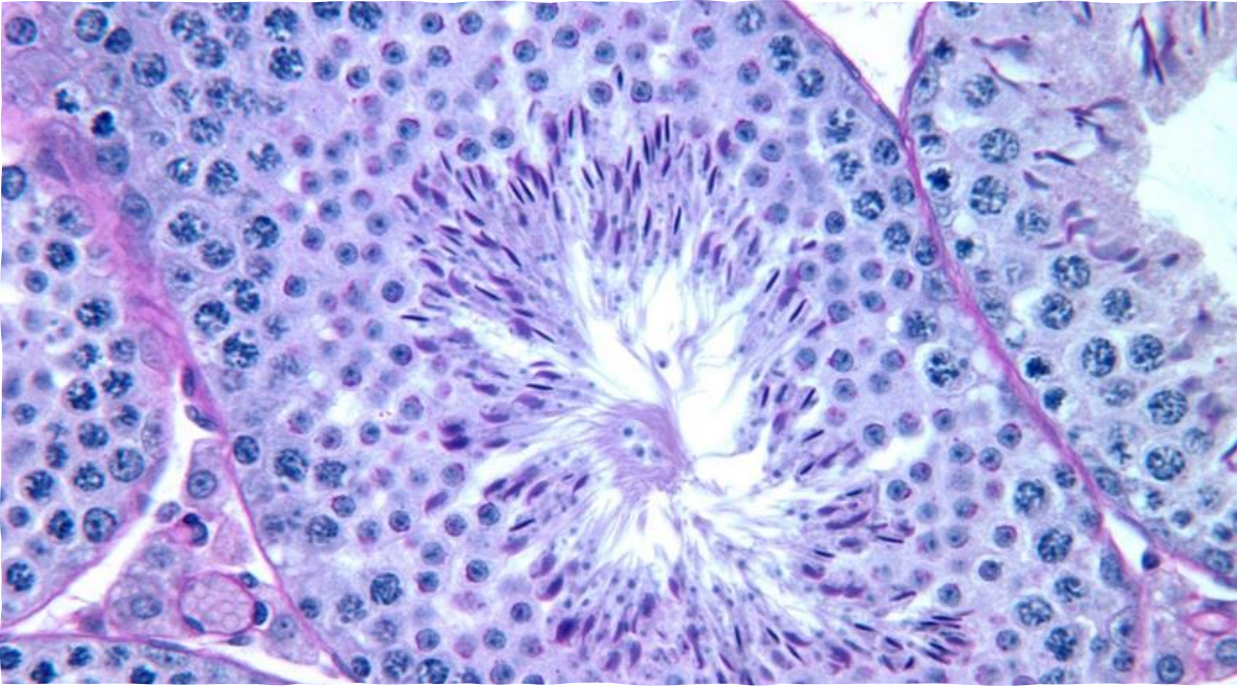

Secondary follicle